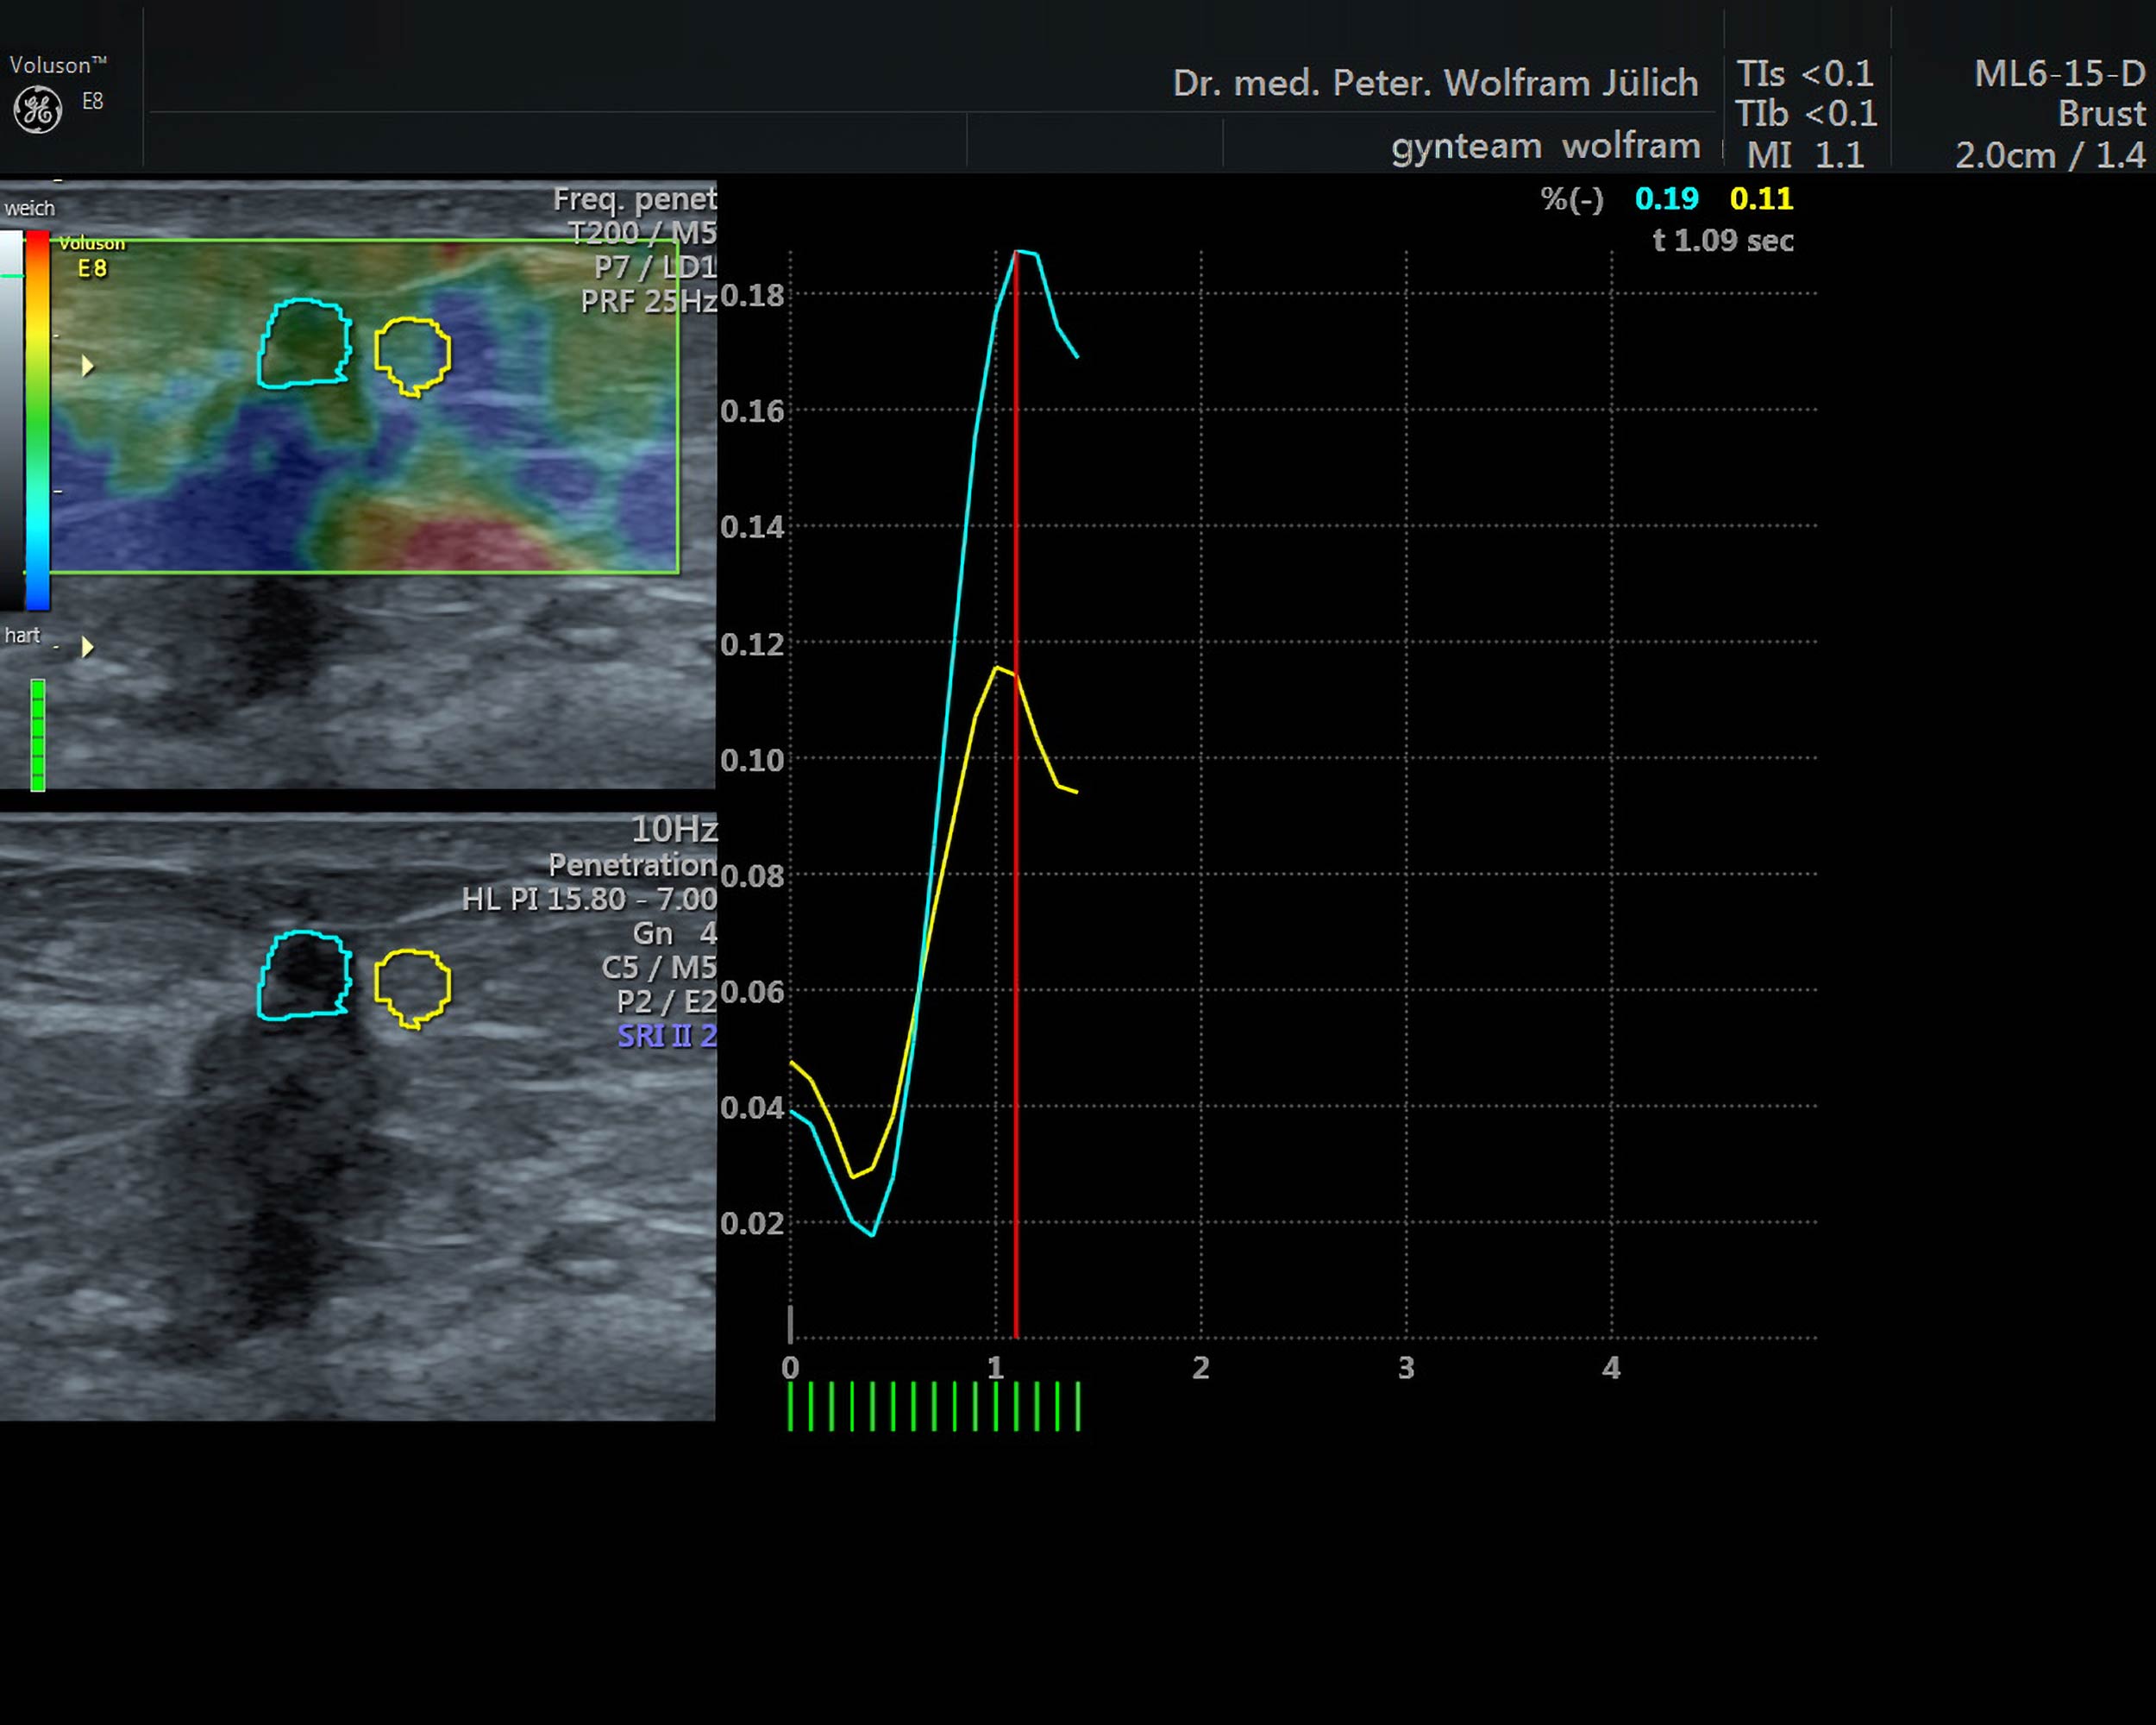

In unseren Praxisräumen nutzen wir ein hochmodernes Ultraschallgerät der neuesten Generation der Voluson-Serie. Es bietet neben einem ultrahochauflösenden Schallkopf  folgende zusätzliche Techniken an::

• 3D-Darstellung mit der Option der Abbildung von Schnittbildern in allen drei Ebenen

• Dopplersonographie (Darstellung von Blutströmen)

• Elastographie (Sichtbarmachung der Gewebekonsistenz)

Diese Zusatztechniken haben eine immer exaktere Abgrenzung zwischen gut- und bösartigen Tumoren ermöglicht.